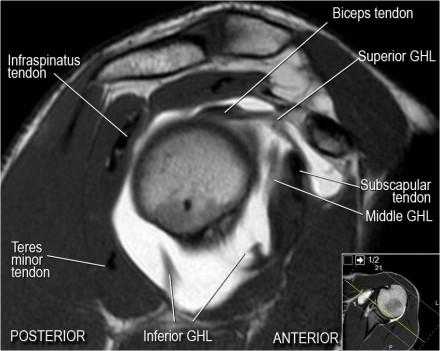

Нормальная анатомия плечевого сустава в аксиальных изображениях и контрольный список.

- поищите os acromiale, акромиальную кость (добавочная кость, расположенная у акромиона)

- обратите внимание что ход сухожилия надостной мышцы параллелен оси мышцы (это не всегда так)

- обратите внимание что ход сухожилия длинной головки двуглавой мышцы в области прикрепления направлен на 12 часов. Область прикрепления может быть различной ширины.

- обратите внимание на верхние отделы суставной губы и прикрепление верхней плече-лопаточной связки. На данном уровне ищется SLAP-повреждение (Superior Labrum Anterior to Posterior) и варианты строения в виде отверстия под сутавной губой (sublabral foramen - подгубное отверстие). На этом же уровне по задне-боковой поверхности головки плечевой кости визуализируются повреждение Хилл-Сакса.

- волокна сухожилия подлопаточной мышцы, создавая бицепитальную борозду, удерживают сухожилие длинной головки двуглавой мышцы. Изучите хрящи.

- уровень средней плече-лопаточной связки и передних отделов суставной губы. Поищите комплекс Буффорда. Изучите хрящи.

- вогнутость заднебокового края головки плечевой кости не следует путать с повреждением Хилл-Сакса, поскольку это нормальная форма для данного уровня. Повреждение Хилл-Сакса визуализируется только на уровне клювовидного отростка. В предних отделах мы сейчас на урвоне 3-6 часов. Здесь визуализируются повреждение Банкарта и его варианты.

- обратите внимание на волокна нижней плече-лопаточной связки. На данном уровне так же ищется повреждение Банкарта.

Нормальная сагиттальная анатомия и контрольный список

- обратите внимание на мышцы манжеты вращателей и поищите их атрофию

- обратите внимание на среднюю плече-лопаточную связку, которая имеет косое направление в полости сустава, и изучите отношение к сухожилию подлопаточной мышцы

- на данном уровне иногда видны повреждения суставной губы в направлении на 3-6 часов

- изучите место прикрепления длинной головки двуглавой мышцы плеча к суставной губе (biceps anchor)

- обратите внимание на форму акромиона

- поищите импинджмент за счет акромиально ключичного сустава. Обратите внимание на интервал между мажетой вращателей и клювовидно-плечевой связкой (coracohumeral ligament).

- поищите повреждение подостной мышцы